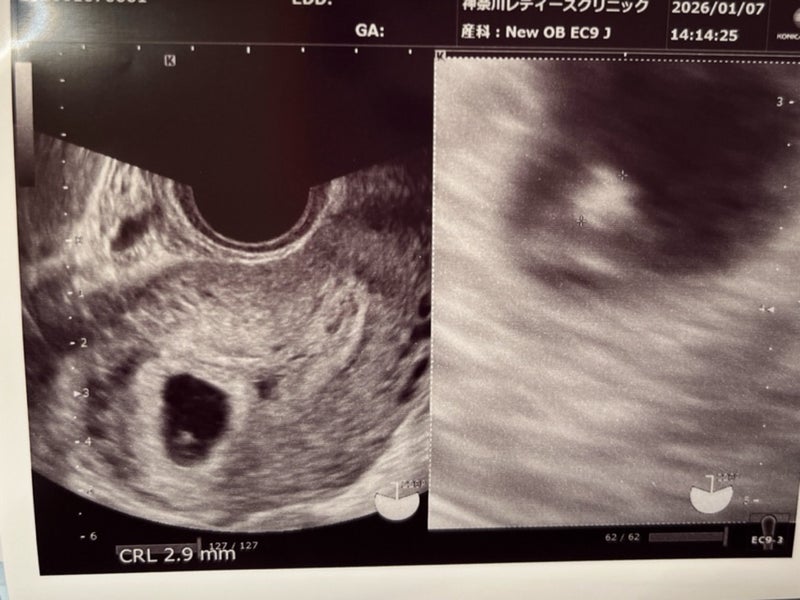

嬉しすぎて泣いた胎児の心拍確認